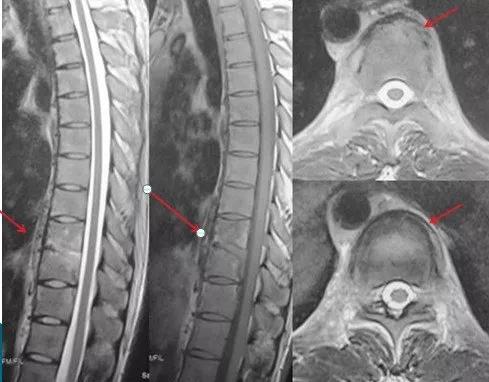

抗结核治疗十八个月后,脓肿已经完全吸收,病灶愈合(红色箭头示)。脊柱生理曲度良好。

因此,部分脊柱结核患者可以通过保守治疗治愈,但保守治疗不是意味着吃上药就好了,需要医生对患者病情有全面评估,制定合理的药物组合方案,并定期复查,根据药物疗效以及副作用等及时调整药物,同时,根据不同治疗阶段的康复指导也很关键。